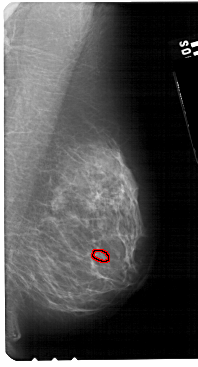

ics_version 1.0 filename A-1310-1 DATE_OF_STUDY 15 8 1995 PATIENT_AGE 48 FILM FILM_TYPE REGULAR DENSITY 1 DATE_DIGITIZED 7 7 1998 DIGITIZER HOWTEK 43.5 SEQUENCE LEFT_CC LINES 5491 PIXELS_PER_LINE 2851 BITS_PER_PIXEL 12 RESOLUTION 43.5 NON_OVERLAY LEFT_MLO LINES 5491 PIXELS_PER_LINE 3166 BITS_PER_PIXEL 12 RESOLUTION 43.5 NON_OVERLAY RIGHT_CC LINES 5491 PIXELS_PER_LINE 2926 BITS_PER_PIXEL 12 RESOLUTION 43.5 OVERLAY RIGHT_MLO LINES 5491 PIXELS_PER_LINE 2956 BITS_PER_PIXEL 12 RESOLUTION 43.5 OVERLAY |

FILE: A_1310_1.RIGHT_CC.OVERLAY TOTAL_ABNORMALITIES 1 ABNORMALITY 1 LESION_TYPE CALCIFICATION TYPE PLEOMORPHIC DISTRIBUTION CLUSTERED ASSESSMENT 4 SUBTLETY 1 PATHOLOGY BENIGN TOTAL_OUTLINES 1 BOUNDARY |